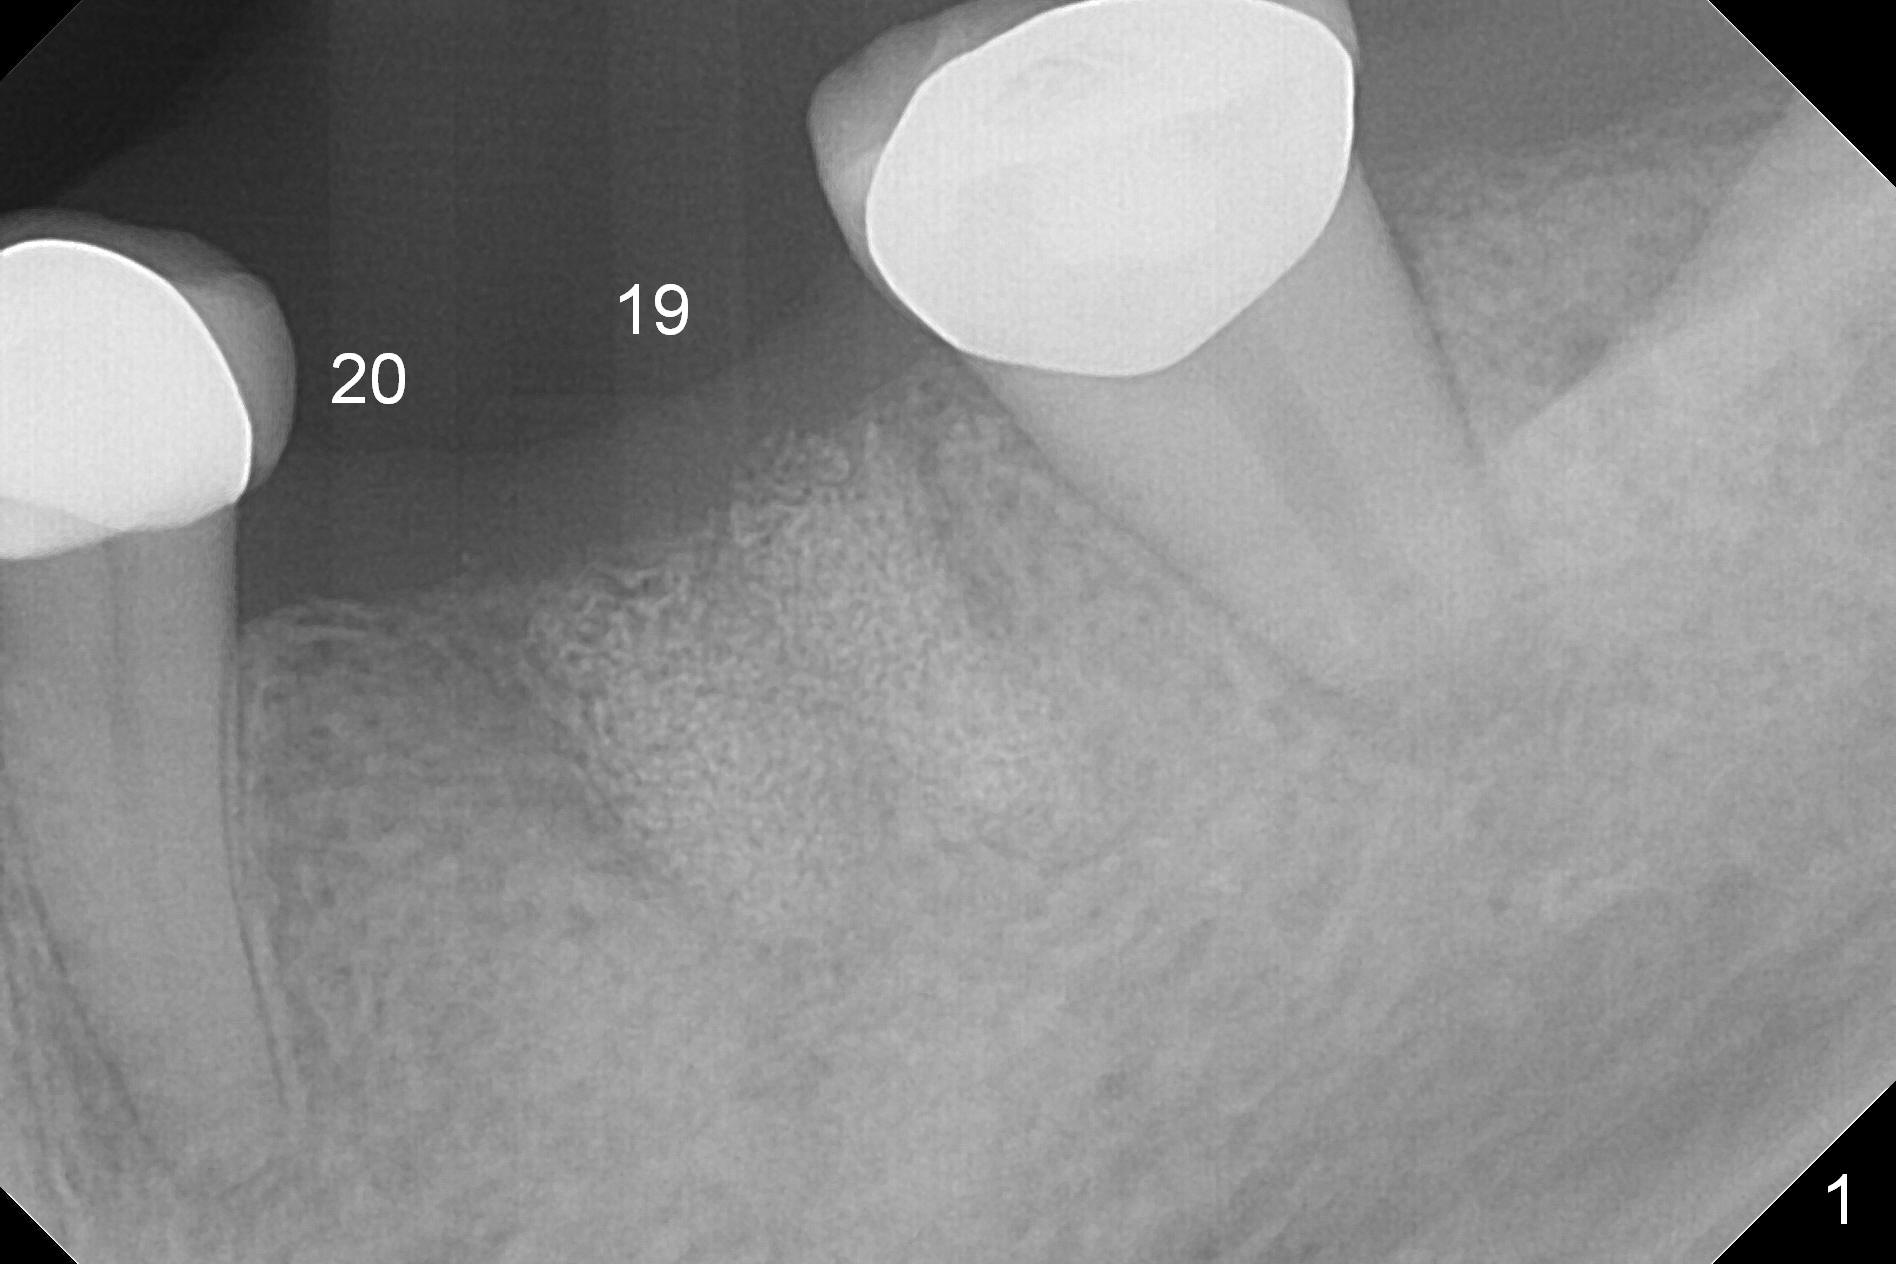

A 54-year-old woman requests implant placement at #19 six months post socket preservation with cow bone (Fig.1). The tooth #20 have been lost much longer. How many implants should be in the edentulous area?